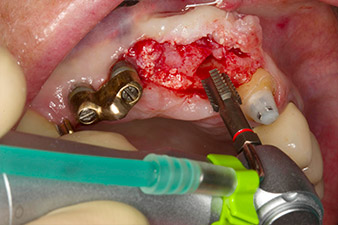

orificio piloto utilizando el nuevo Implantmed y el contra-ángulo WS-56 L

Imagen 2: Dos meses después, se practicó un orificio piloto utilizando el nuevo Implantmed y el contra-ángulo WS-56 L (programa P1, transmisión 1:1). La refrigeración se realizó a través del tubo de spray colocado a la izquierda (para diestros).

El hueso alveolar de la posición 22 resultó tener unas dimensiones suficientes. Las figuras 2 y 4 muestran la preparación del lecho del implante, el corte de rosca y la colocación del implante con el equipo Implantmed.